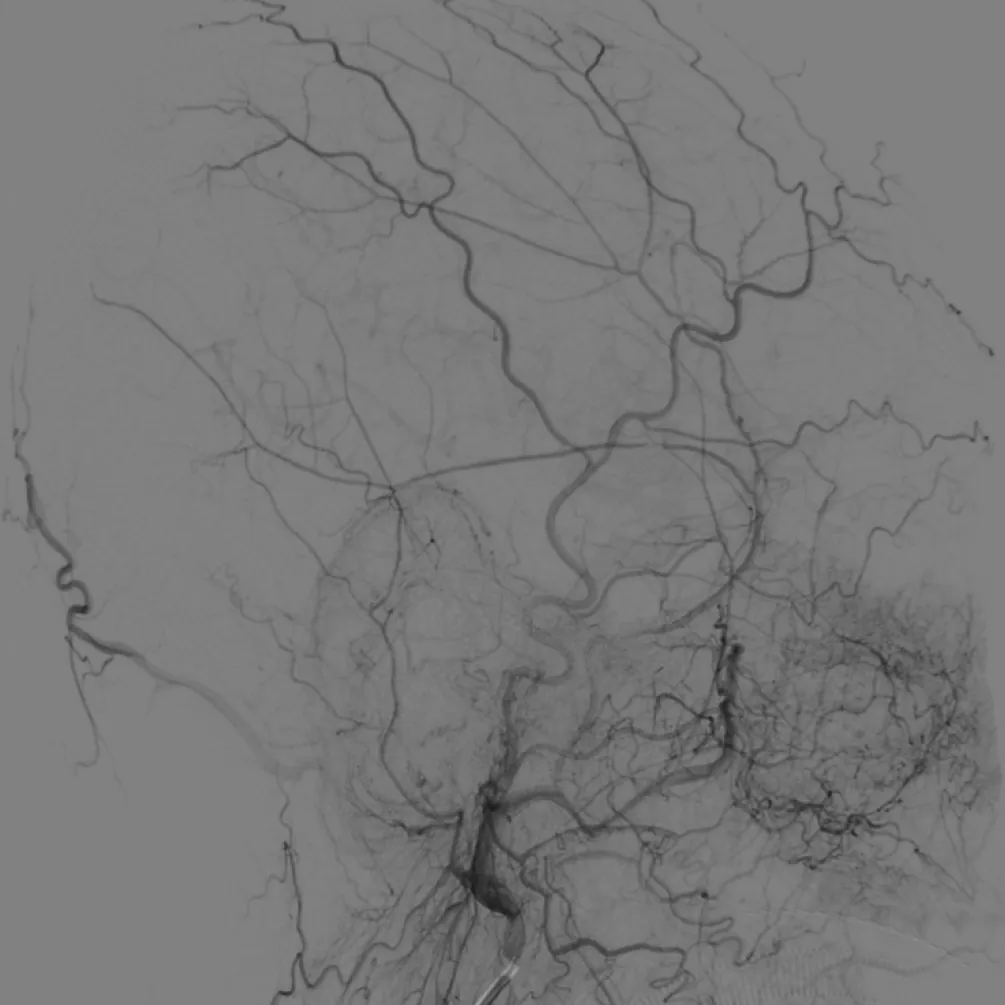

术前造影

右颈内造影

左颈内造影

右颈外无异常

左颈外无异常

左颈总造影,未见异常供血

右颈外造影,可见右侧蝶腭动脉分支供血,但无良好路径显示

右颈内造影,可见右侧眼动脉-筛后动脉供血,见经额底静脉-双侧额部皮层静脉向上矢状窦方向引流